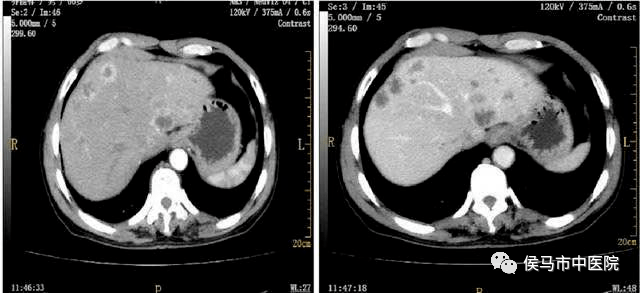

8、CT增强

该设备超清的图像质量,超高的分辨率,对病灶定性能力高,对小病灶的检出率高,尤其适合颅脑、颈部、胸部、腹部、盆腔等实质脏器的检查。